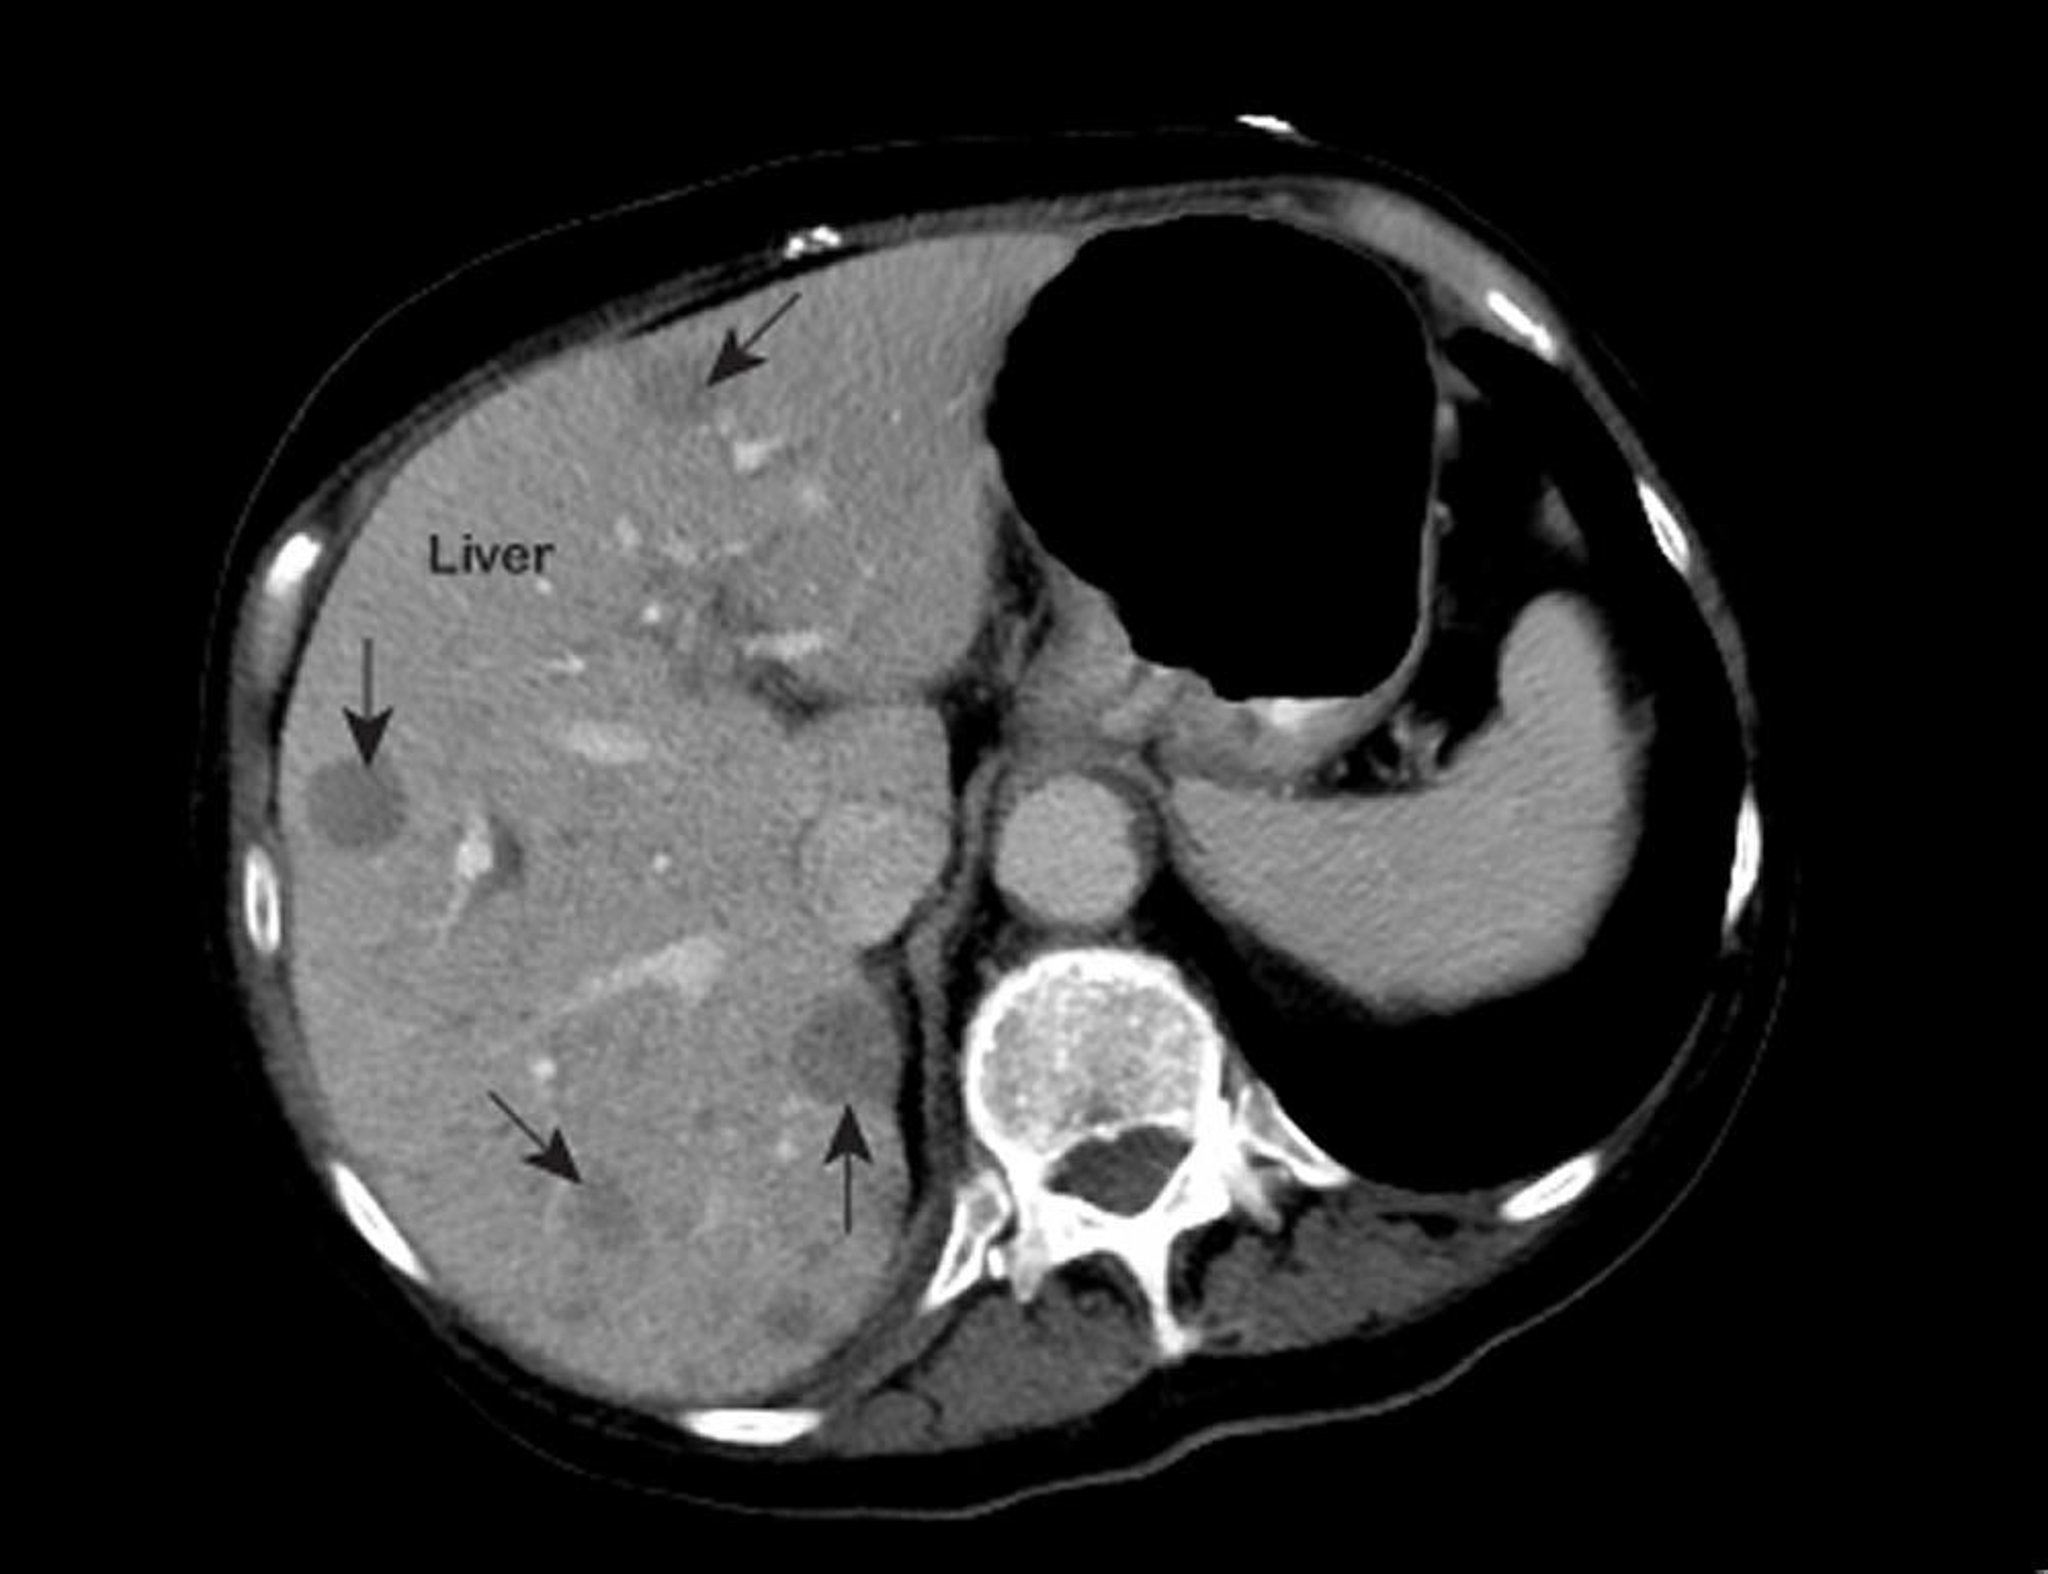

비정상적인 흉부 자기공명영상(MRI)에서는 간 내부의 비정상 부위(화살표로 표시)를 보여줍니다. 이 소견은 전이성 간암에 일반적입니다.

사진 제공: 의학박사 패트릭 오케인(Patrick O’Kane).